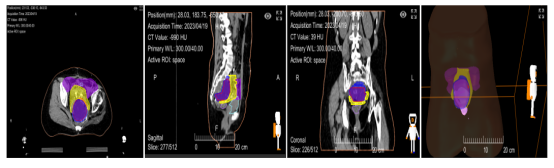

重(碳)离子治疗靶区勾画,瘤体与危及器官间手术置入隔离组织物,为目标肿瘤与周围正常组织提供了足够的距离,从而可以给肿瘤以充足的根治剂量。

手术将肿瘤与肠管间置入纱扩垫,隔开肠管,保护肠管,当天完成重离子灭活肿瘤

靶区勾画:GTV-红色 结肠-紫色 隔离组织物-黄色